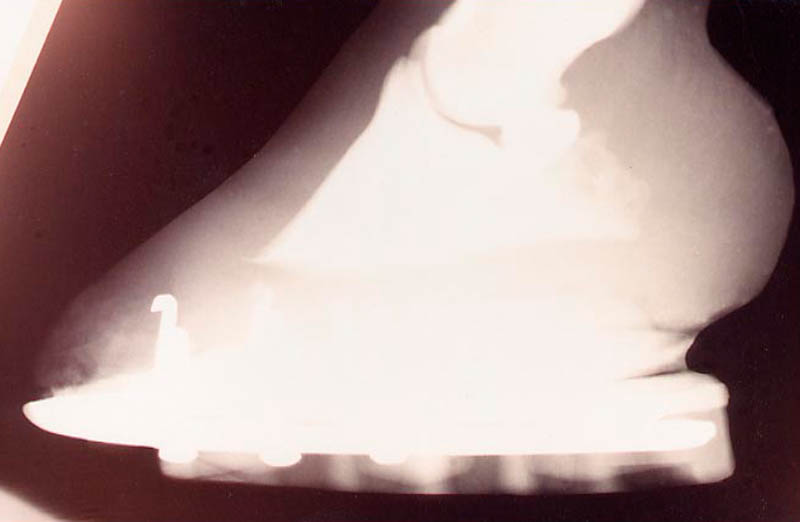

• Trim heels lower to position P3 level with ground

• Trim the walls level with or shorter than the sole

1. Maintain a reduced load on the wall until the new wall and laminae are grown (8 to 14 months). It should be noted that the displaced hoof wall, as such, cannot be reattached. Repair can only occur through the process of normal hoof wall growth. Once the wall is unloaded, the new wall generating from the coronary band becomes attached with healthy laminae as the growth progresses toward the ground.

Two to four months: There now is approximately one inch (1") of new wall growth from the coronary band which is closely connected to the coffin bone with healthy laminae. The horse may walk almost normal but is noticeably careful. There is a possibility of recurring problems with inflammation (serum fluid pressure).

Three to six months: One and one half inches (1 1/2") of stable new wall growth. The horse is comfortable. It walks freely and sometimes trots and lopes. There is a risk that the horse may feel so good that it will run around and tear the laminae again. Excessive traveling may cause the sole to be overloaded, resulting in sole bruises and inflammation. Keep the horse content with a quiet pen mate.

Eight months: Two inches (2") of new wall growth. The horse is quite sound. It is tempting, at this time, to relax the treatment and to overwork the feet. Do not quit now!

Twelve to Fourteen months: Complete new hoof wall grown out to the ground. The horse is sound with a normal healthy hoof structure. The horse can resume normal performance. The feet can be managed with normal trimming or shoeing. With some chronic cases, complete rejuvenation is limited due to the existence of permanent damage to the laminae and/or the blood supply to the laminae or coronary band. However, those feet can still become quite stable and can be managed with a lesser degree of sole support on a continuous basis.